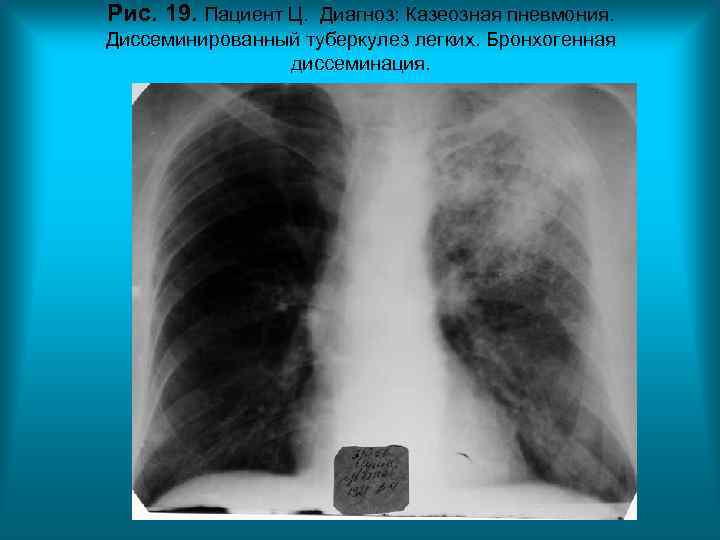

Рис. 19. Пациент Ц. Диагноз: Казеозная пневмония. Диссеминированный туберкулез легких. Бронхогенная диссеминация.